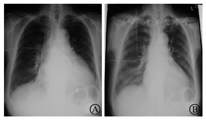

入院检查:血、尿、便常规、肝肾功能、凝血、感染指标(-);NT-proBNP 6 398 pg/ml、肌钙蛋白I(-);甲状腺功能、免疫固定电泳(-);血沉、C反应蛋白、类风湿因子、抗核抗体、抗双链DNA抗体、补体、抗中性粒细胞胞浆抗体(-);外周大动脉超声(-);冠状动脉CT血管造影(CTA)未见冠状动脉明显钙化及狭窄。心力衰竭治疗上除继续利尿外,予地高辛、氯沙坦、螺内酯治疗,此后在心力衰竭症状稳定的前提下加用低剂量美托洛尔;心房颤动治疗上先予毛花甙C、地高辛控制心室率,逐渐上调美托洛尔剂量(琥珀酸美托洛尔23.75 mg 1次/d渐加至71.25 mg 1次/d),给予阿司匹林。心室率从150次/min逐渐平稳降至70次/min。4周后复查胸部X线片显示心脏大小较前明显缩小(图1);超声心动图提示自第3周开始LVEF(57%)、左心大小改善(左心房48 mm,左心室舒张末径56 mm),4周后恢复正常(LVEF 60%,左心房40 mm,左心室舒张末径52 mm)。NT-proBNP降至852 pg/ml;6 min步行距离为415 m。

A:入院时;B:治疗4周后